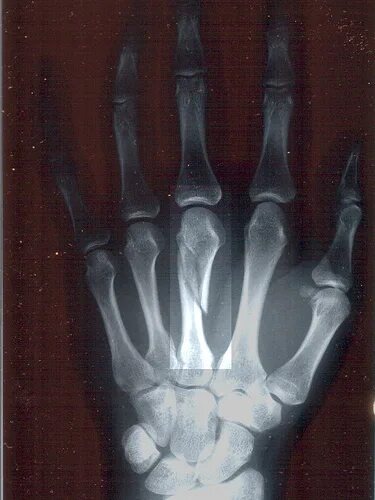

Чтобы подтвердить диагноз, врач проведёт осмотр и назначит рентгеновское исследование. Это поможет не только подтвердить наличие перелома, но и определить его тип (например, закрытый или открытый) и степень повреждения.

Пястные кости — это пять костей, которые расположены между запястьем и фалангами пальцев. Они образуют основную часть руки, обеспечивая поддержку для пальцев и кисти в целом. Пястные кости необходимы для того, чтобы рука могла эффективно выполнять различные движения, такие как хватание, поднимание и манипуляции с предметами.

Перелом пястной кости чаще всего происходит в области основы или тела кости, реже — в области головки.